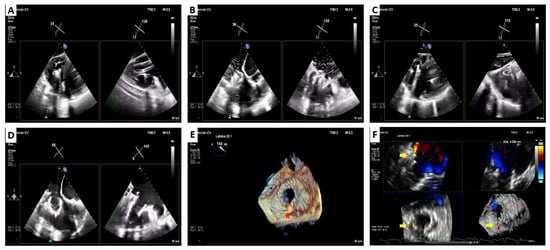

3. Lux-Valve Plus Case